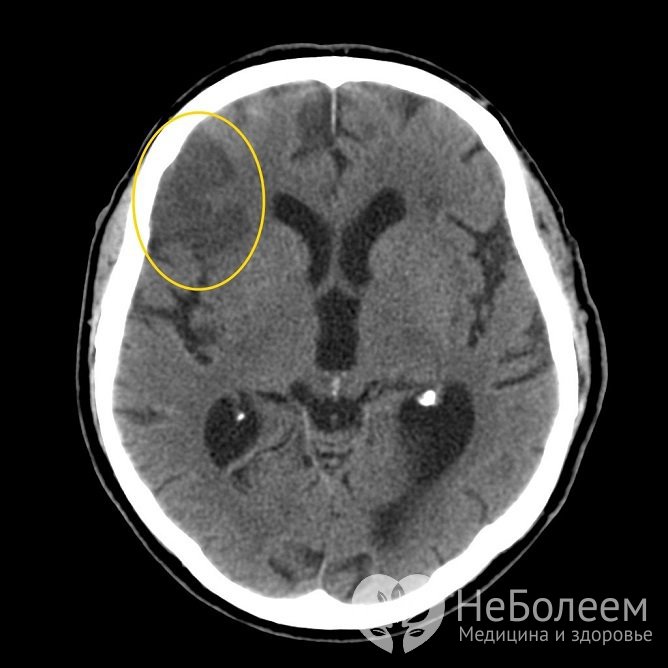

Ишемический инсульт на КТ